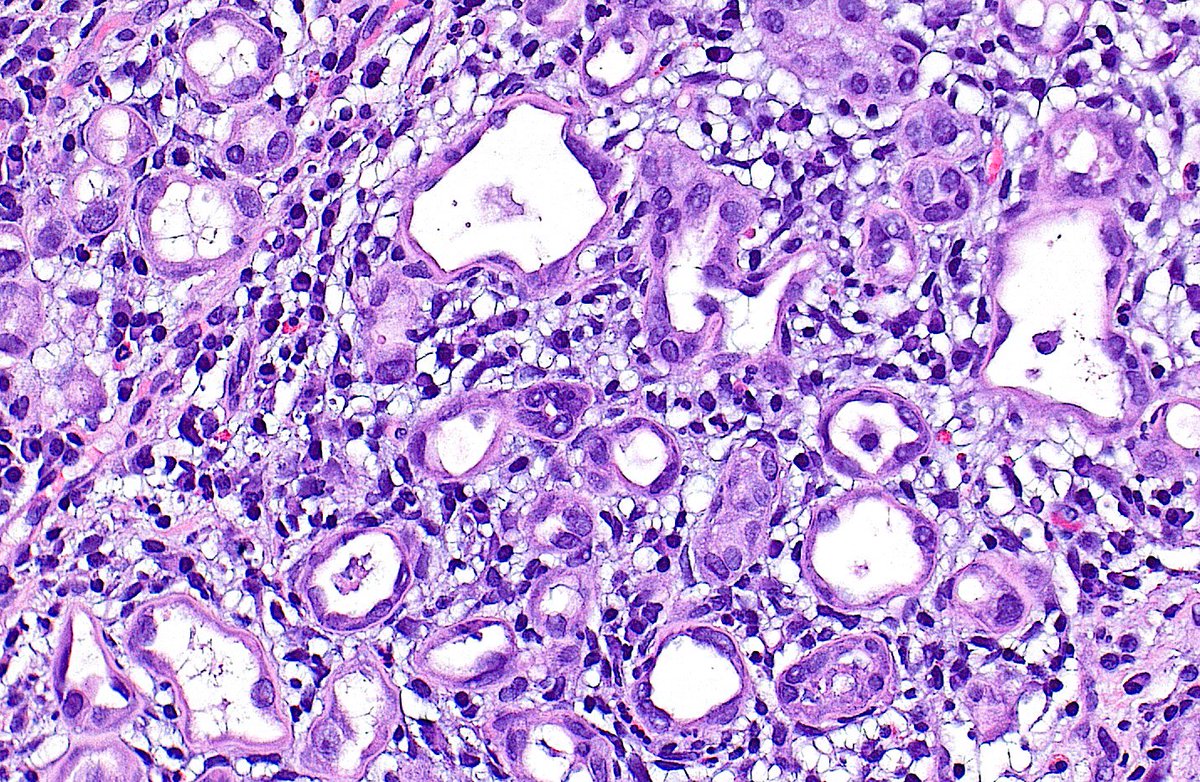

The proceedings of the first ever consensus conference on #urachal neoplasms, held under the auspices of ISUP International Society of Urological Pathology, is now published! Congratulations to all! #GUPath Paper is freely available as open access👇👇👇 pubmed.ncbi.nlm.nih.gov/40471793/